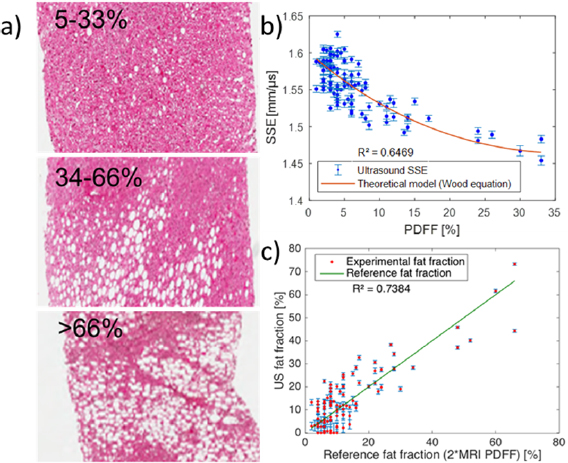

For the 100 patients, the estimated acoustic sound speeds ranged from 1450 m s−1 to 1625 m s−1. To illustrate the increasing number of hepatocytes with triglyceride accumulation along with steatosis grade and the accompanying range of sound speeds, one example with three different patient biopsies is presented in figure 5(a). For each patient, the relationship between SSE values obtained using ultrasound and the fat fraction obtained from MRI-PDFF was compared to the theoretical equation (5). The theoretical prediction based on equation (5) was plotted on the same graph (figure 5(b)) using known physical values from the literature for fat and healthy liver densities (respectively  = 800 kg m−3 and

Figure 5. Clinical quantification of fat fraction in patients using ultrasound. (a) Histology images of biopsied tissue from three different patients with mild (macroscopic steatosis in 5% to 33% of hepatocytes) to severe (macroscopic steatosis in more than 66% of hepatocytes) steatosis. One clearly notices the increasing number of hepatocytes with triglyceride accumulation. (b) Quantitative estimation of the acoustic sound speed in N = 100 patients. (c) Quantitative ultrasound fat fraction using adaptive SSE compared to the reference fat fraction (2 * MRI PDFF).

Standard image High-resolution imageAgain, the measurements were found to be in good agreement (R2 = 0.65) with the theoretical curve (figure 5(b)). Using equation (7) applied to SSE estimates, the ultrasonic fat fraction was found to be in good agreement (R2 = 0.74) with the fat fraction deduced from MRI-PDFF (figure 5(c)). The Bland Altman analysis between ultrasonic fat fraction and the MRI fat fraction gives an arithmetic mean difference of ± 41.8% and a 95% confidence interval of the mean difference ranging between 22.9% and 60.6%.